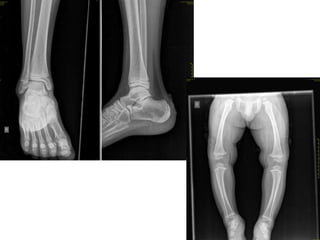

• For age estimation, usually standard right sided

X-rays are taken in AP view

-with few exceptions elbow (AP and Lat)

• Selection of regions/joints:

for age 6-12 years  elbow and wrist

for age 13-16 years  elbow and pelvis

• Wrist (& hand) is most studied region by

foreign authors/researchers.